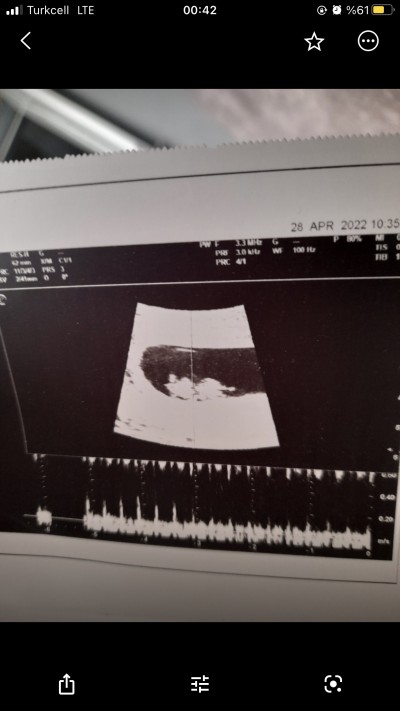

image

Minnoş bi kız zannımca çünkü erkek bebekler kendıni cok cabuk bellı edıyorlar benm oglandan biliyorum

Birinci foto sekız ıkıncı foto 12 haftalık ne kadar bellı elı kolı bacagı uzuvları